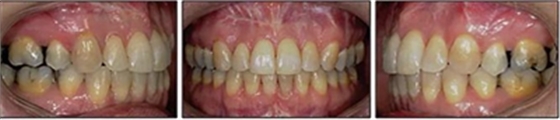

患者側(cè)貌改善,下唇唇肌緊張消失,上下唇可自然閉合。磨牙及尖牙關(guān)系糾正至I類(lèi),覆合覆蓋正常。上下頜弓型糾正至卵圓形,牙弓寬度增加。頭影測(cè)量分析示SNA角81.8°,ANB角3°。頭影測(cè)量重疊圖示下頜骨向后旋轉(zhuǎn),垂直面高度略有增加。

19個(gè)月后復(fù)查,情況穩(wěn)定,牙弓寬度穩(wěn)定。